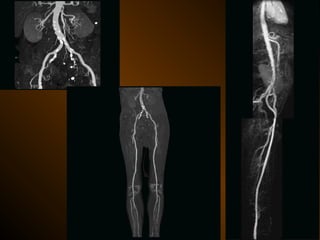

QUANG MẠCH

• Chỉ định giới hạn

X QUANG CAN THIỆP

Dẫn lưu áp xe bụng

Thủ thuật nghẽn mạch cầm máu